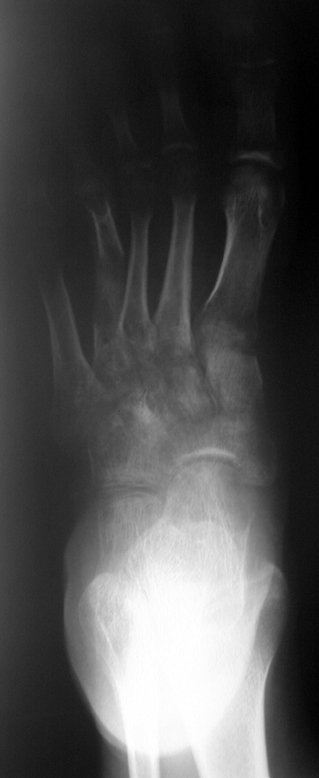

El parmağı (metakarp) ve ayak parmağı (metatars) kısalıkları doğuştan tek başına, geniş bir sendrom grubuyla birlikte, travma sonrası, Freiberg hastalığı (avasküler nekroz) sonrası görülebilir.

Doğuştan metakarp ve metatars kısalığının görülme sıklığı 1/1000’den azdır. Kadınlarda erkeklere göre 5 kat daha fazla görülür ve sıklıkla (%72) iki taraflıdır. En sık 4. parmak tutulur. Bu tür olgularda sorunun nedeni tam olarak bilinmemekle brlikte deformitenin genellikle epifiz plağının erken kapanmasından kaynaklandığı düşünülmektedir.

Metakarp kısalığında kozmetik görünümün bozulması ve dominant elin kullanımı sırasında yorulma, metatars kısalığında ise kozmetik haricinde metatarsalji, kısa parmağın dorsale kayması sonucu deformite oluşması, plantar yönde açılanması sonucu ağrı ve bası ülserleri, ve ayakkabı giymede zorluk nedeniyle ameliyat gerekebilir.

Doğuştan metakarp ve metatars kısalıklarının redavisi için pek çok teknik tanımlanmakla birlikte en çok akut uzatma sonrası kemik uçlarına greft konması ve distraksiyon osteogenezi (kallotasis) kullanılmaktadır. 1 cm.den daha fazla uzatma gereken olgularda kallotasis yöntemi önerilmektedir. Kliniğimizde de metatars ve metakarp uzatma için unilateral eksternal fiksatör ve sirküler eksternal fiksatör yardımıyla distraksiyon osteogenezi yöntemi tercih edilmektedir.